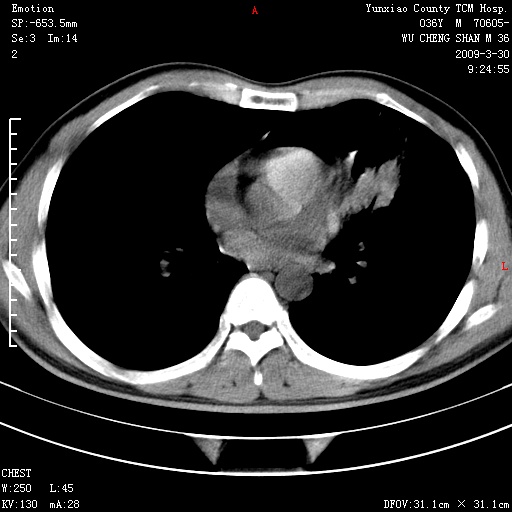

本院家属,胸痛,无咳嗽咳痰发烧病史,治疗一个月后病灶无明显改变,支气管镜示左肺慢性炎症,未见癌细胞,

临床资料不全,就影像资料来看,诊断炎性病变应该不错,肺结核?如果硬要考虑肺泡癌 证据不足!

建议:1)上传全部资料 观察纵隔内情况 2)完善实验室检查。

胸痛,无咳嗽咳痰发烧病史,治疗一个月后病灶无明显改变,支气管镜示左肺慢性炎症,未见癌细胞,左肺下叶前段片状影,边缘不清,内见空支气管征,纵隔未见淋巴结肿大,周围无卫星灶,应考虑为炎性病变。